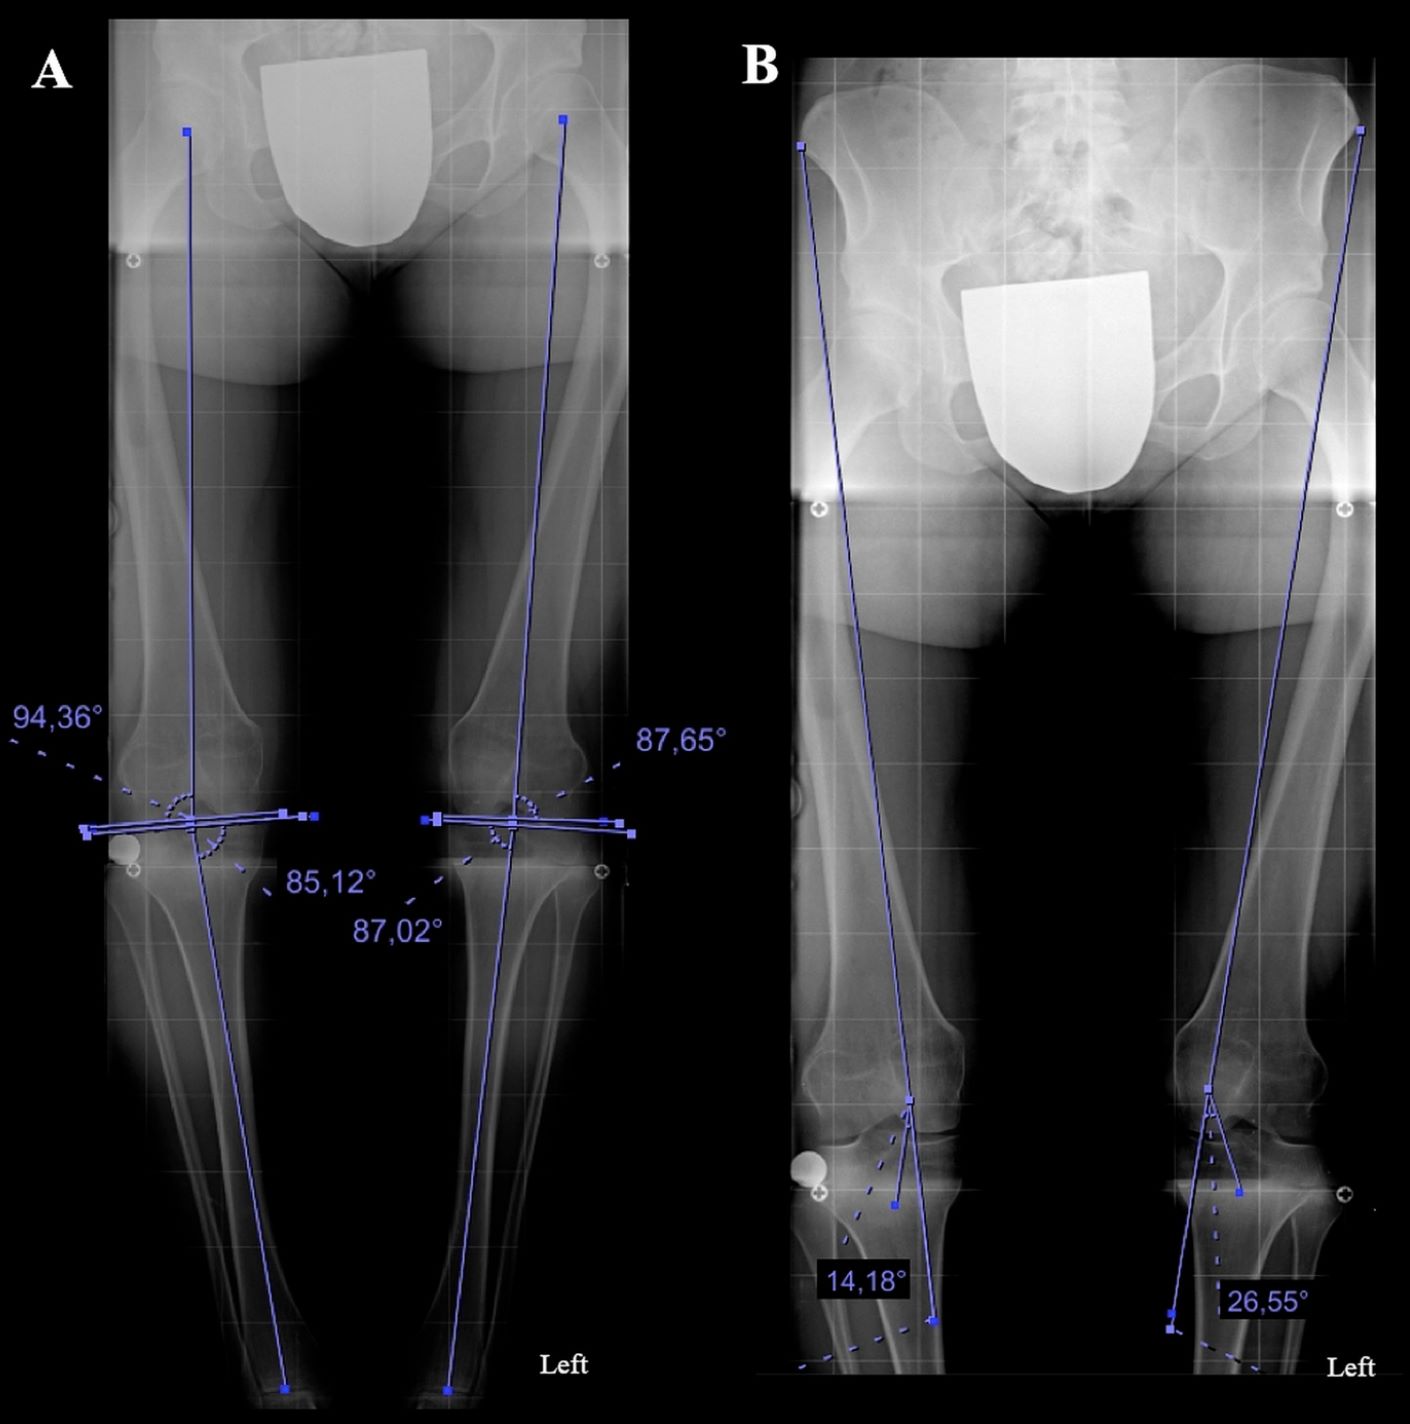

Una mujer de 19 años con dolor persistente anterior de rodilla fue diagnosticada con una deformidad torsional compleja tibial y femoral (26 ° de anteversión femoral y 49 ° de rotación externa tibial). Para lograr la correcta realineación del miembro inferior, fueron necesarias doble osteotomías rotacionales. Después de planificar la corrección en la tomografía computarizada y el modelo tridimensional (3D), se produjo un sistema de guía impreso en 3D a medida para respaldar la cirugía.

El modelo de planificación impreso en 3D y el sistema de guía quirúrgica son elementos cruciales para lograr resultados óptimos en casos complejos de mala alineación. Las guías «a medida» llevaron a una combinación perfecta entre la corrección planificada y el resultado intraoperatorio.